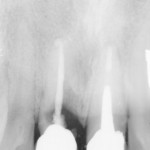

Aumento verticale di cresta mediante innesto autologo in zona estetica

Riassunto

L’atrofia della cresta alveolare, in senso sia verticale sia orizzontale, è l’esito della perdita di elementi dentali dovuta a estrazioni, carie, traumi o motivi...